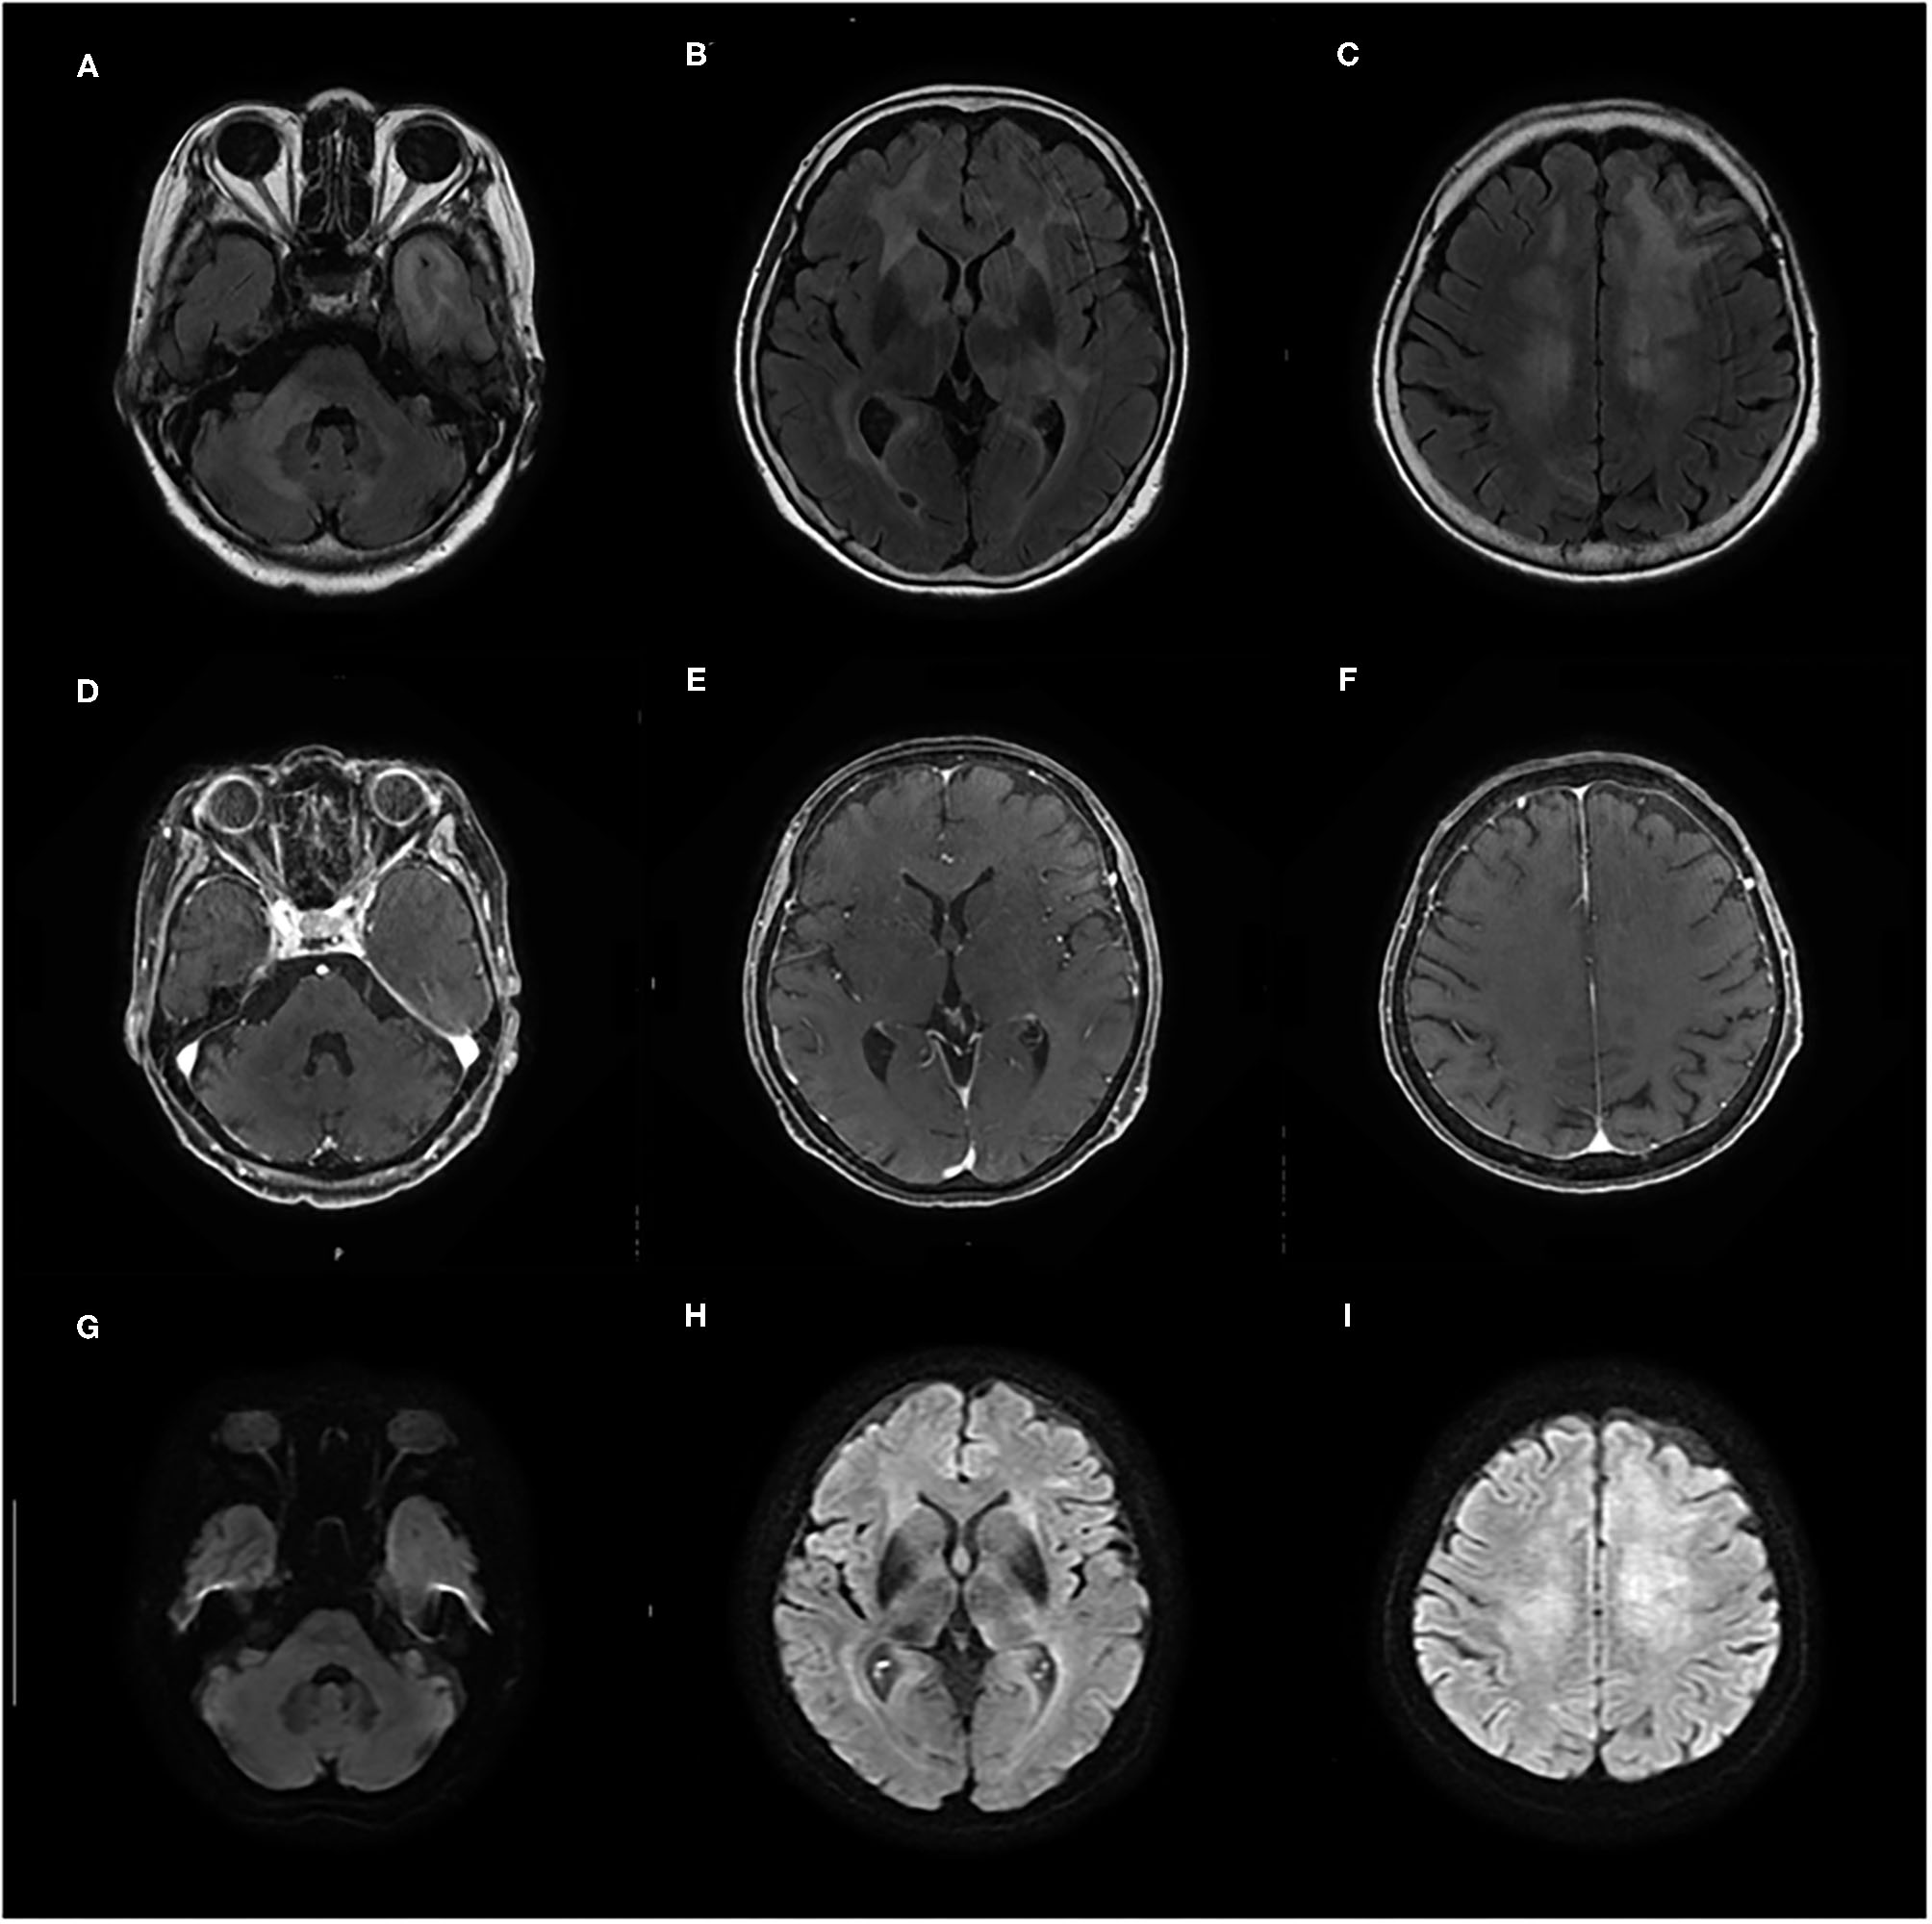

Initial laboratory tests did not reveal any specific abnormalities. Complete blood count, liver function, and renal function were within the reference range (RR). Thyroid function was in a euthyroid state, and no elevation of serum anti-TPO antibody and anti-Tg antibody was observed in electrochemiluminescence immunoassay (<9.0 and <10.8 IU/ml, respectively; RR <16.0 and <28.0 IU/ml, respectively). The concentrations of lactate dehydrogenase (LDH) and soluble interleukin-2 receptor (sIL-2R) were not elevated (134 IU/L and 206 U/ml, respectively; RR = 100–220 IU/L and 121–613 U/ml, respectively), and human immunodeficiency virus was negative. Cerebrospinal fluid (CSF) analyses showed elevated total protein levels (TP = 52 mg/dl, RR = 10–40 mg/dl) and slightly high levels of sIL-2R (61 U/ml, RR <60.4 U/ml); however, the LDH concentration was 42 U/ml (RR = 8–50 U/ml). CSF analyses also demonstrated normal cell counts (1 leucocyte/μl) without atypia and no amplification of polymerase chain reaction for the John Cunningham (JC) virus. Brain MRI on initial presentation revealed diffuse non-enhancing T2/fluid-attenuated inversion recovery hyperintense lesions in the bilateral cerebral white matter, left temporal pole, and right middle cerebellar peduncle (Figures 1A–F). On diffusion-weighted imaging (DWI), these lesions showed faintly high intensities; however, they could be explained by T2 shine-through (Figures 1G–I).

Figure 1. (A–F) Contrast-enhanced brain MRI taken on admission shows diffuse T2/fluid-attenuated inversion recovery (FLAIR) hyperintense lesions in bilateral cerebral white matter, left temporal pole, and right middle cerebellar peduncle without gadolinium enhancement. (G–I) On diffusion-weighted imaging (DWI), these lesions show faintly high intensities that can be explained by T2 shine-through.